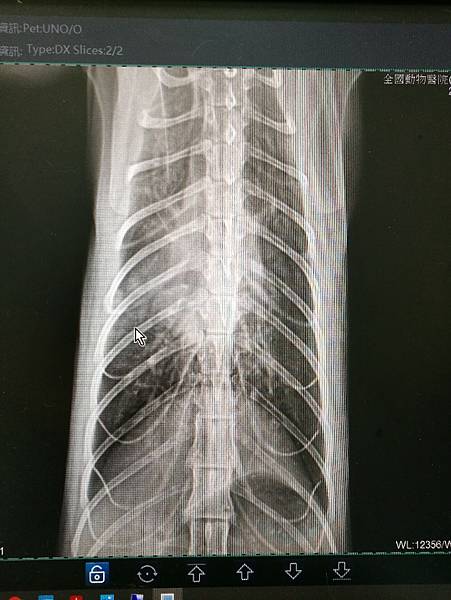

但就是要請醫院這邊提供X光片跟血檢還有用藥資料!